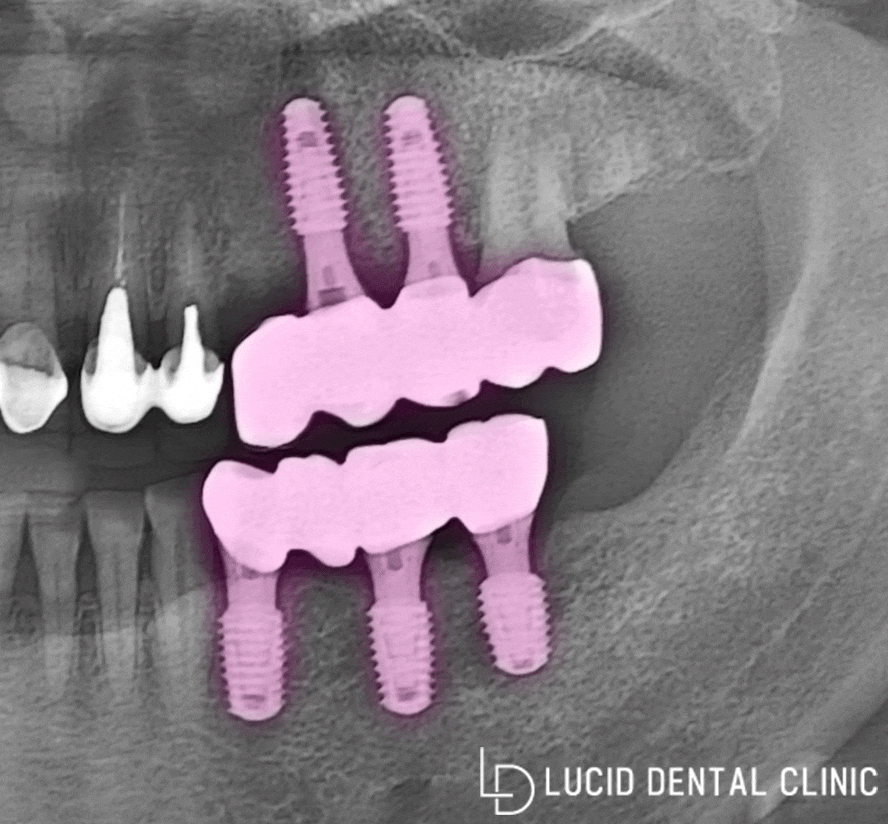

위와 같이 최종 보철 체결까지 마치고

파노라마 엑스레이로 확인해 봤습니다.

계획한 위치에 맞게 잘 식립된 모습과

소실된 치아 기능을 대체할 수 있도록

튼튼한 재질의 최종 크라운 보철까지,

조화로운 모습을 확인할 수 있었죠 :)